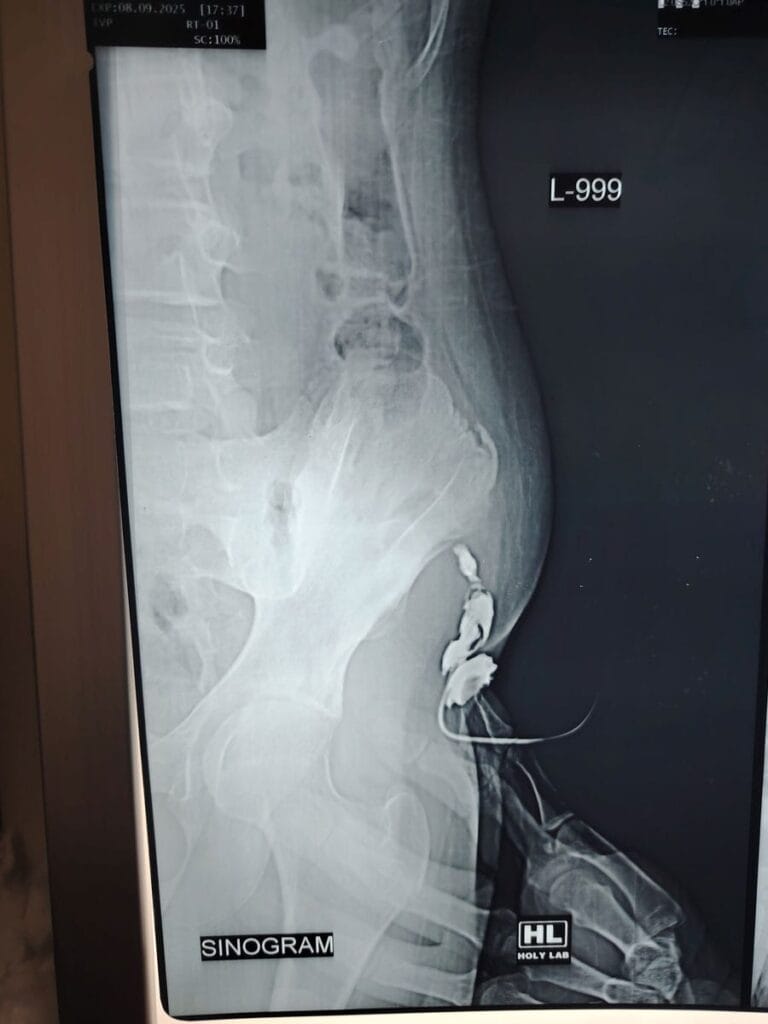

- Different types of cyst, sinus and fistula